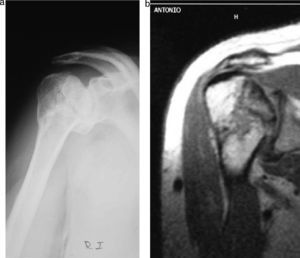

Los criterios de inclusión fueron las fracturas en 2, 3 y 4 fragmentos impactadas en valgo o varo (fig. 1) con o sin luxación asociada y tratadas percutáneamente.

Las pruebas de imagen realizadas fueron radiografía simple en proyecciones antero-posterior y perfil escapular. En todos se asoció estudio TC y en los últimos 4 años reconstrucciones 3D.

Hubo 15 sujetos que presentaron complicaciones (17%). De ellas 4 fueron necrosis avasculares confirmadas por RM, 3 consolidaciones viciosas por mala posición de algún fragmento de la fractura, 3 migraciones de agujas, 3 capsulitis adhesivas, 1 consolidación insuficiente y 1 lesión iatrógena del nervio radial.

De las necrosis avasculares, que supusieron el 4% de todos los casos, una fue en una fractura en 3 partes (2,2%) y 3 en fracturas en 4 partes (12%). Si sólo consideramos las fracturas en 3 y 4 partes (69 casos) el porcentaje de necrosis avasculares ascendió al 5,7%.

Otra complicación, la necrosis avascular producida por falta de riego sanguíneo en un segmento óseo, aparece entre el primer y segundo años y suele asentar en el cuadrante supero-externo de la cabeza humeral, donde las solicitaciones mecánicas son más importantes22 (fig. 6).

Los TC y 3D pueden ayudar a orientar el pronóstico24. En nuestra revisión, llegamos al diagnóstico de los casos tras sospecha clínica y radiológica confirmada con RM. Las fracturas en 3 partes tuvieron un 2,2% de necrosis y las de 4 partes un 12%, sin presentarse en las fracturas en 2 partes, lo que daría en un total de 69 fracturas (5,7%). Estas cifras bajas pueden estar influidas por la rigurosa selección de casos y una técnica quirúrgica cuidadosa que evite lesionar el precario aporte sanguíneo.